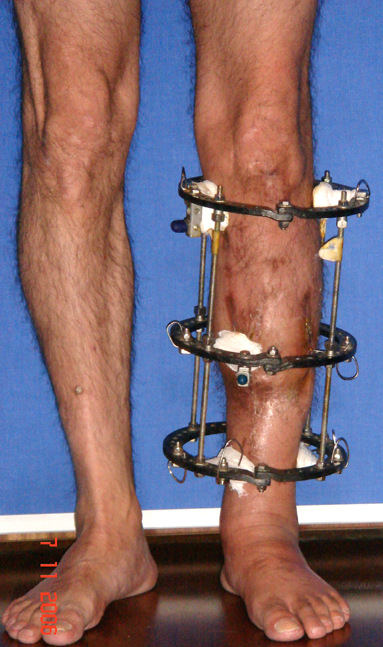

Uygun radikal debridman tüm nekrotik kemik ve yumuşak dokuların çıkartılmasını gerektirir, ve sıklıkla uzuvda instabiliteye neden olur. Kalan kemik ve yumuşak doku defektinin bir şekilde fiksasyonu ve rekonstrüksiyonu gereklidir. İlizarov’un ortaya koyduğu distraksiyon osteogenezi yöntemi, kaynamanın elde edilmesi, deformitenin düzeltilmesi, bacak boy eşitsizliğinin giderilmesi ve segmental defektlerin rekonstrükte edilmesi için başarıyla kullanılmaktadır.

Eksternal fiksatör ile geçen süre (eksternal fiksasyon indeksi), gereken distraksiyon miktarına bağlıdır ve bu süre boyunca bazı komplikasyonlarla karşılaşılabilir. Distraksiyon dönemi sona erdikten sonra, distraksiyon süresinin iki katını aşan konsolidasyon döneminde hastalar eksternal fiksatörü zorlukla tolere edebilirler. Yeterli konsolidasyon sağlanmadan eksternal fiksatör çıkartılırsa ise kırıklar, deformite ve kısalık oluşabilir. Hastanın fiksatör ile birlikte geçirdiği sürenin azaltılması ve böylece hasta konforunun ve aktivite düzeyinin arttırılması için intramedüller çivi üzerinden uzatma yöntemi uygulanmaktadır. Bu yöntemde distraksiyon dönemi sona erdiğinde kemiğin içindeki çivi statik olarak kilitlenmekte ve eksternal fiksatör çıkartılmaktadır. Stabilizasyon intramedüller çivi tarafından sağlandıktan sonra konsolidasyon dönemi gerçekleşmektedir. Bu şekilde hem eksternal fiksatörün uzun süre kalmasından hem de erken çıkartılmasından kaynaklanan komplikasyonların önüne geçilmektedir.